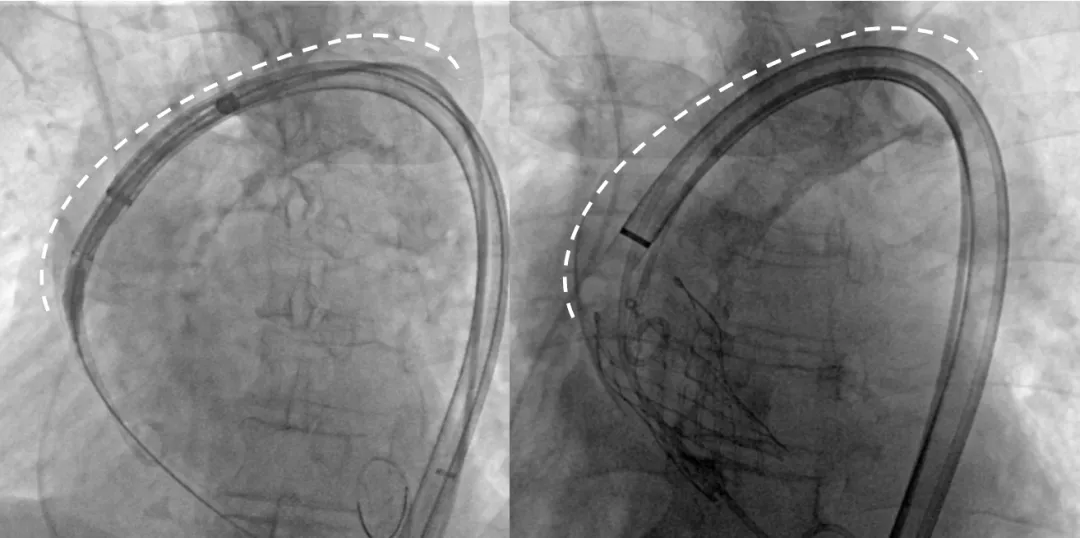

Step 2.建立大鞘通路:大鞘通过升主、边进入边加弯,避免剐蹭弓部斑块

Step 4.输送系统进入:过弓性能优异,悬空通过,整体过程未将鞘管顶起至弓顶部

过弓示意图

手术中其实有个关键点,在可调弯鞘过弓的时候,我们特意放慢了速度,一遍进一遍调弯,确保每一步都不触碰弓顶钙化。这台手术的成功,本质上是 “病变特点和器械特性” 的精准匹配。对同类型来说,碰到瓷化升主动脉合并复杂弓的病例,建议术前一定要把钙化范围、弓部角度这些解剖细节分析透,器械选择上不用局限于单一方案,多考虑协同作用,或许能找到更安全的路径。毕竟对我们来说,每台复杂手术的目标都一样:在保证安全的前提下,给患者带来最好的长期获益。